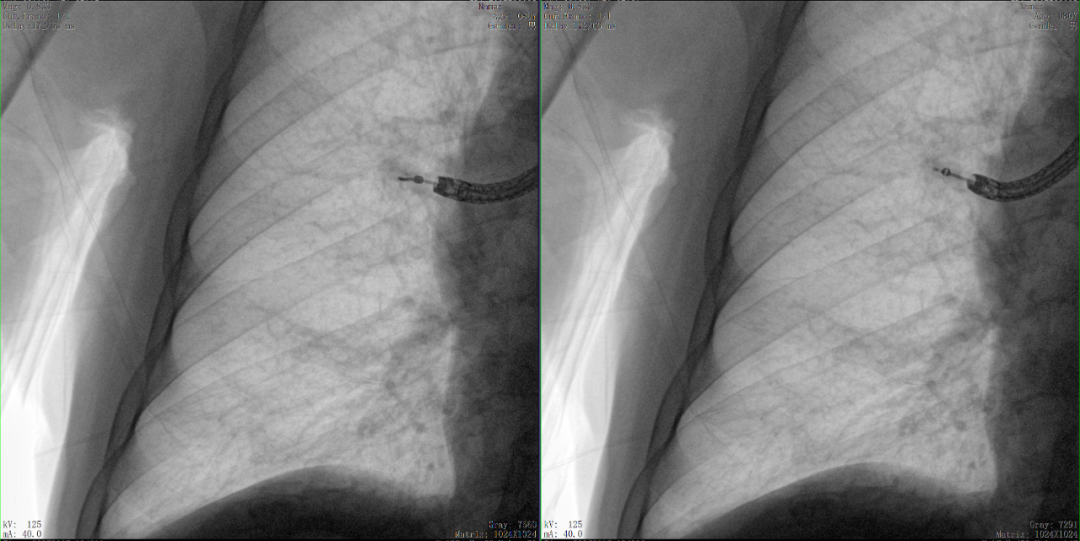

病例2 踝關節骨折復位(31歲)

在踝關節骨折復位手術中,用三維C可以更好地觀察骨折部位的復位情況:

正側位影像觀察脛腓聯合復位良好

從三維影像看,復位欠佳,貼合度不夠